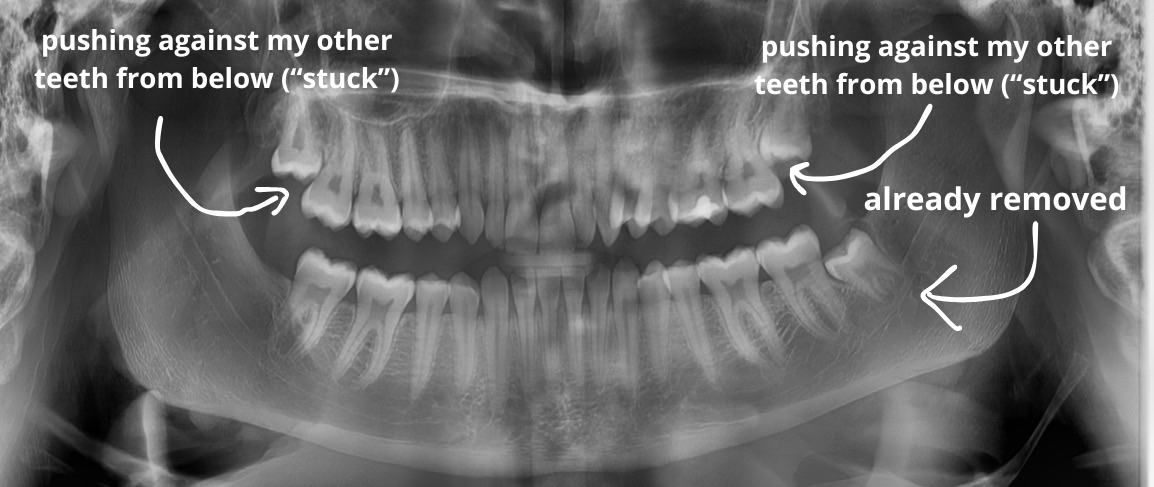

So recently I got my lower wisdom tooth removed, because only one managed to grow. (I am nearly 21 now, with a very narrow mouth if that matters)

Now the question is - should I have my top ones removed, since they're pushing onto my other teeth from below, and might be "squishing" them all together. (they also haven't even cut through the skin - they're genuinely stuck down there)

My jaw x-ray before getting the bottom one removed:

My jaw x-ray before getting the bottom one removed: